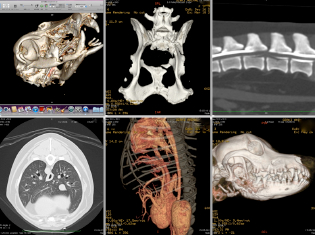

CT検査室

おざき動物病院では、2013 年病院のリニューアルと同時にCT を新しくしました。

GE(ゼネラルエレクトリック)製16 列ヘリカルCT という装置で、以前よりも短時間で撮影ができ、診断能力も格段に向上しました。

CT ではレントゲンでは見つからなかった腫瘍や、頭の中を撮影することができます。

また3D 画像を構築して手術前にシュミレーションを実施し、より正確で安全な手術ができるようになりました。